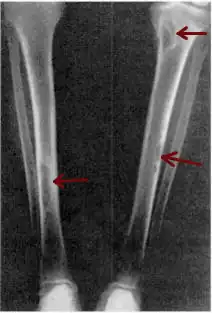

| Osteitis fibrosa cystica of the tibia. Arrows point to the brown tumors which are typically present in bones of people with OFC. | |

Osteitis fibrosa cystica (/ˌɒstiˈaɪtɪs faɪˈbroʊsə ˈsɪstɪkə/ OSS-tee-EYE-tis fy-BROH-sə SIS-tik-ə) is a skeletal disorder resulting in a loss of bone mass, a weakening of the bones as their calcified supporting structures are replaced with fibrous tissue (peritrabecular fibrosis), and the formation of cyst-like brown tumors in and around the bone. Osteitis fibrosis cystica (OFC), also known as osteitis fibrosa, osteodystrophia fibrosa, and von Recklinghausen's disease of bone (not to be confused with von Recklinghausen's disease, neurofibromatosis type I), is caused by hyperparathyroidism, which is a surplus of parathyroid hormone from over-active parathyroid glands. This surplus stimulates the activity of osteoclasts, cells that break down bone, in a process known as osteoclastic bone resorption. The hyperparathyroidism can be triggered by a parathyroid adenoma, hereditary factors, parathyroid carcinoma, or renal osteodystrophy. Osteoclastic bone resorption releases minerals, including calcium, from the bone into the bloodstream, causing both elevated blood calcium levels, and the structural changes which weaken the bone. The symptoms of the disease are the consequences of both the general softening of the bones and the excess calcium in the blood, and include bone fractures, kidney stones, nausea, moth-eaten appearance in the bones, appetite loss, and weight loss.